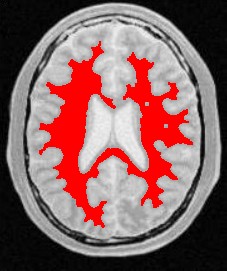

使用人体大脑截面图作为输入图像,选择合适的像素点作为种子像素,生长的结果如下图所示:

| 原始图像 | 连续阈值法 | 邻接连续阈值法 | 置信连接阈值法 |

| 参数 | [150,180] | [150,180] R:3 | Iter:10 factor:2.5 r:5 |

| 结果点数 | 15011 | 7854 | 14643 |